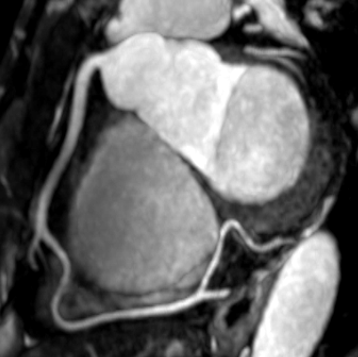

冠動脈MRA

冠動脈MRAは放射線被ばくや造影剤を使用することなく、心臓の血管(冠動脈)を明瞭に描出することができる検査方法です。冠動脈MRAは、高度石灰化症例でも動脈内腔の描出が可能であり、血管の走行異常の確認や血管が動脈硬化によって細くなっている状態を立体(3D)画像を作成して診断を行います。放射線や造影剤を用いることなく診断が可能なため、患者様のお身体のご負担が少なく、なおかつ心臓の病気の早期診断、早期治療に役立てられます。